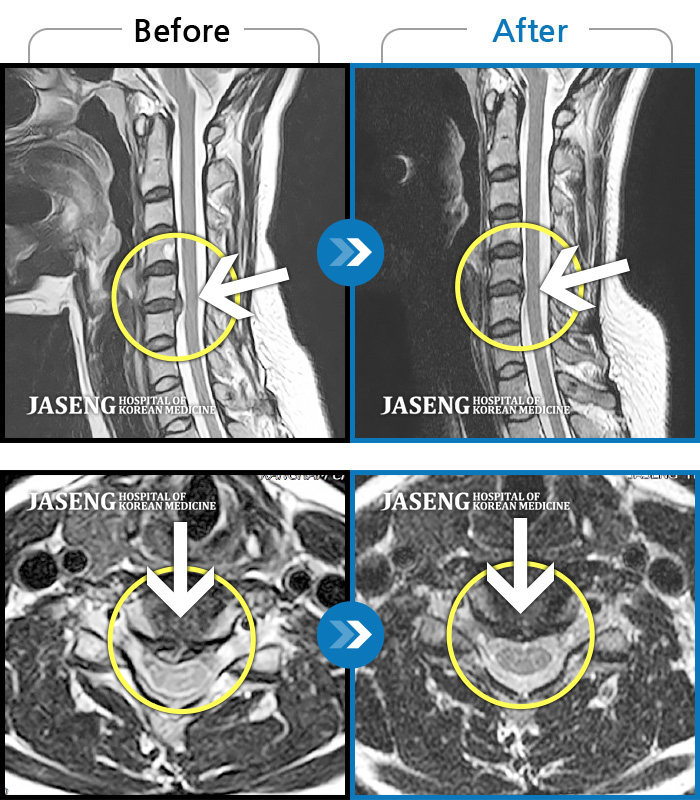

목디스크

많이 본 사례

강남 · 강만호 원장

좌측 목 통증과 좌측 팔저림이 심해서 업무가 힘들었습니다.

촬영시기

2023.07.19 ~ 2024.07.20

2024.07.25

조회수 190